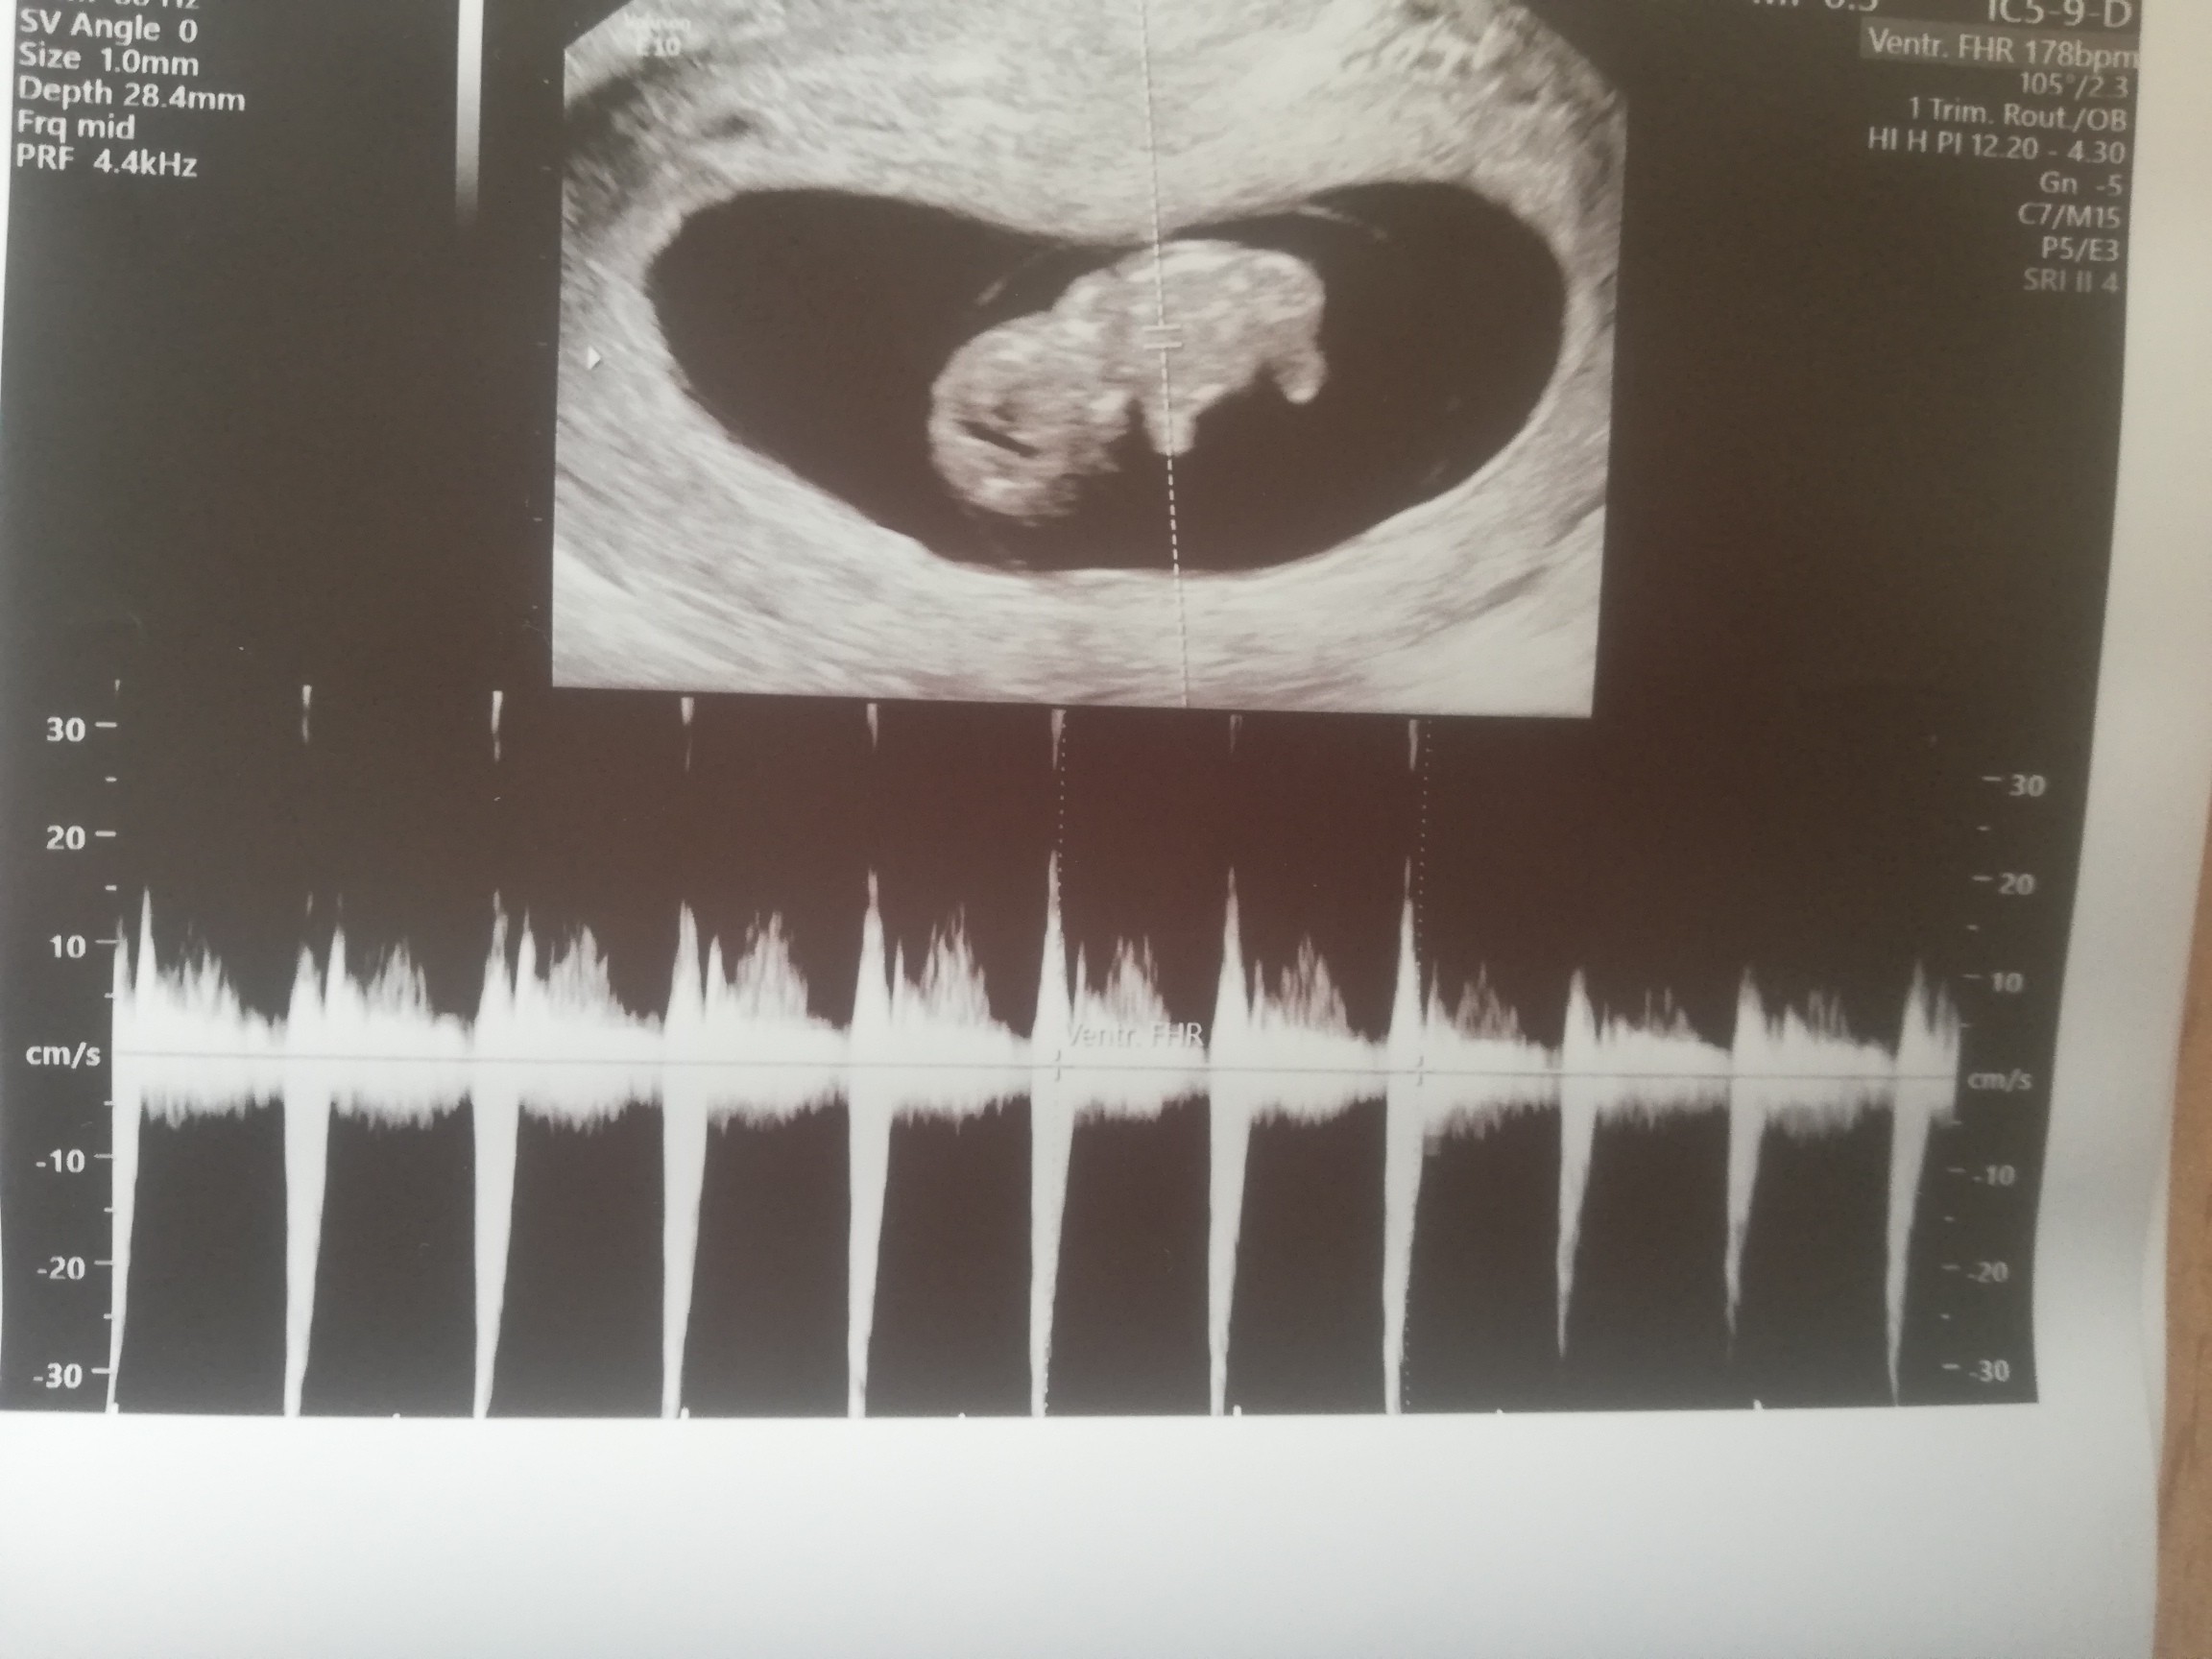

Ja już po wizycie, jest dzidziuś z rączkami i nóżkami i serduszko bije 178, słyszałam pierwsze bicie serca 😍 No jestem szczęśliwa bo nie wierzyłam że będzie dobrze po tej poniedziałkowej wizycie gdzie serduszko bilo 96..już tą ciążę spisałam na starty aż mi głupio że tak pomyślałam przez chwilę :(

Załączniki

• IMG_20220519_181626.jpg

IMG_20220519_181626.jpg

410,9 KB · Wyświetleń: 102